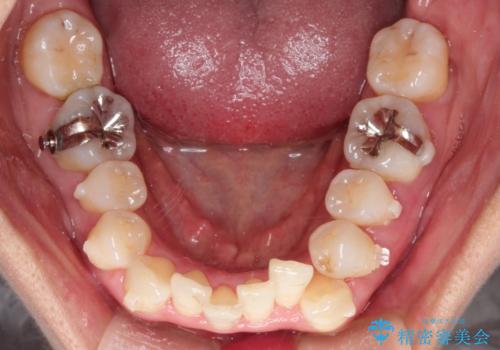

重度のガタガタのインビザラインによる非抜歯矯正

しっかりとマウスピースを使用していただけたので、順調に治療を終えることができました。